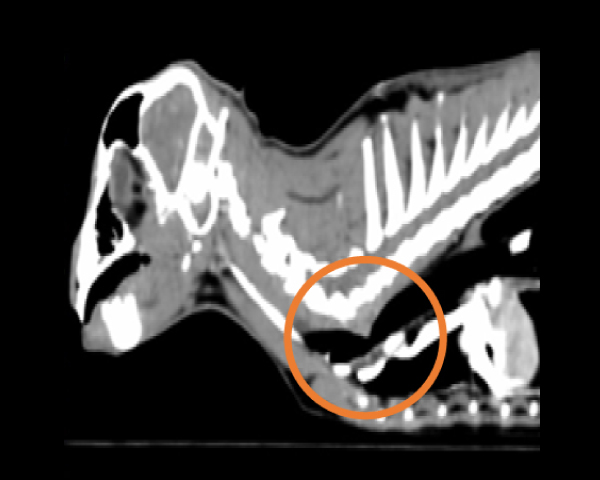

無麻酔CT検査にて結石の個数を確認

無麻酔CT検査にて異物の確定